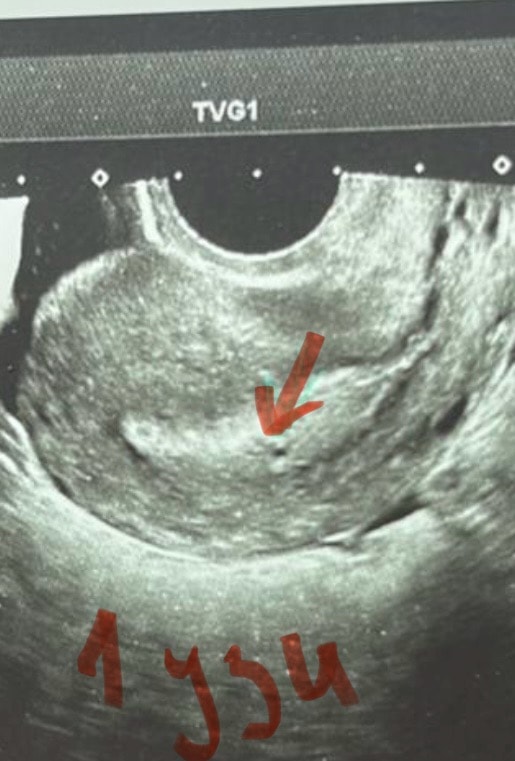

УЗИ пя 4 мм

Обследования, узи, анализыДевочки, всем привет 👋 может было у кого так, у меня акушерский срок 5 недель 4 дня. по узи (на 33 день от начала месячных) маленькая точечка где-то 1 мм ( поставили под вопросом маточную беременность )Хгч на 37 день 171,. Была на узи сегодня (40 день) пя 4,03 мм , и жт в левом яичнике 17мм. Говорит, ждем, чтобы малышарик набирался сил и мы его наконец-то увидели. Пугает, что она говорит, что странно всё на таком сроке, маленькое пя. Но цикл у меня всегда был не регулярный (СПЯК) , поэтому я даже не могу сказать, сколько у меня задержка и когда была О. Может было так у кого, поделитесь своей историей, а то я что-то переживаю после слов врача